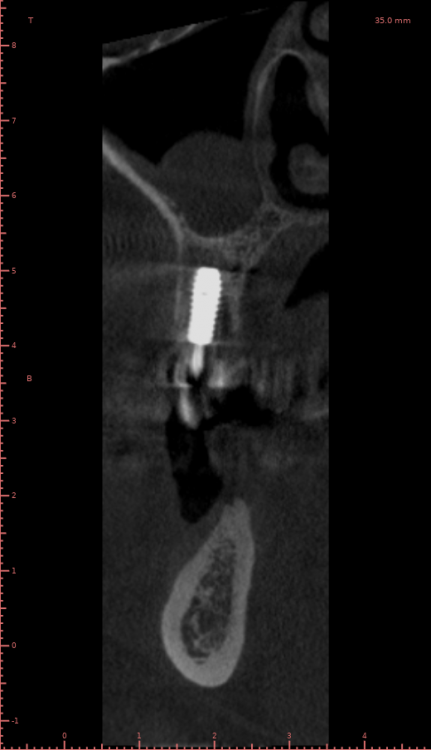

Женька Опубликовано 21 июля, 2021 Автор Поделиться Опубликовано 21 июля, 2021 3 месяца минуло... клык на торке 30 неприятные ощущения второй премоляр на 10 и подвижность... отправил на кт. Всё насмарку... Ссылка на комментарий

Борис80 Опубликовано 21 июля, 2021 Поделиться Опубликовано 21 июля, 2021 премоляр в любом случае недозаглубитом болеет... Ссылка на комментарий

Женька Опубликовано 2 августа, 2021 Автор Поделиться Опубликовано 2 августа, 2021 2.5 с тупым перкуторным звуком И вишенка, нет АРБУЗИЩЕ, на торте 2.3 в соседней теме в ортопедии посоветовали перестать уничтожать людям зубы, тоже самое помоему можно сказать и по хирургии... Правильно же понимаю, что протезировать такой (2.3) не стоит. Даже если торк выдержит в 35 чревато проблемами после установки постоянной ортопедии. Ссылка на комментарий